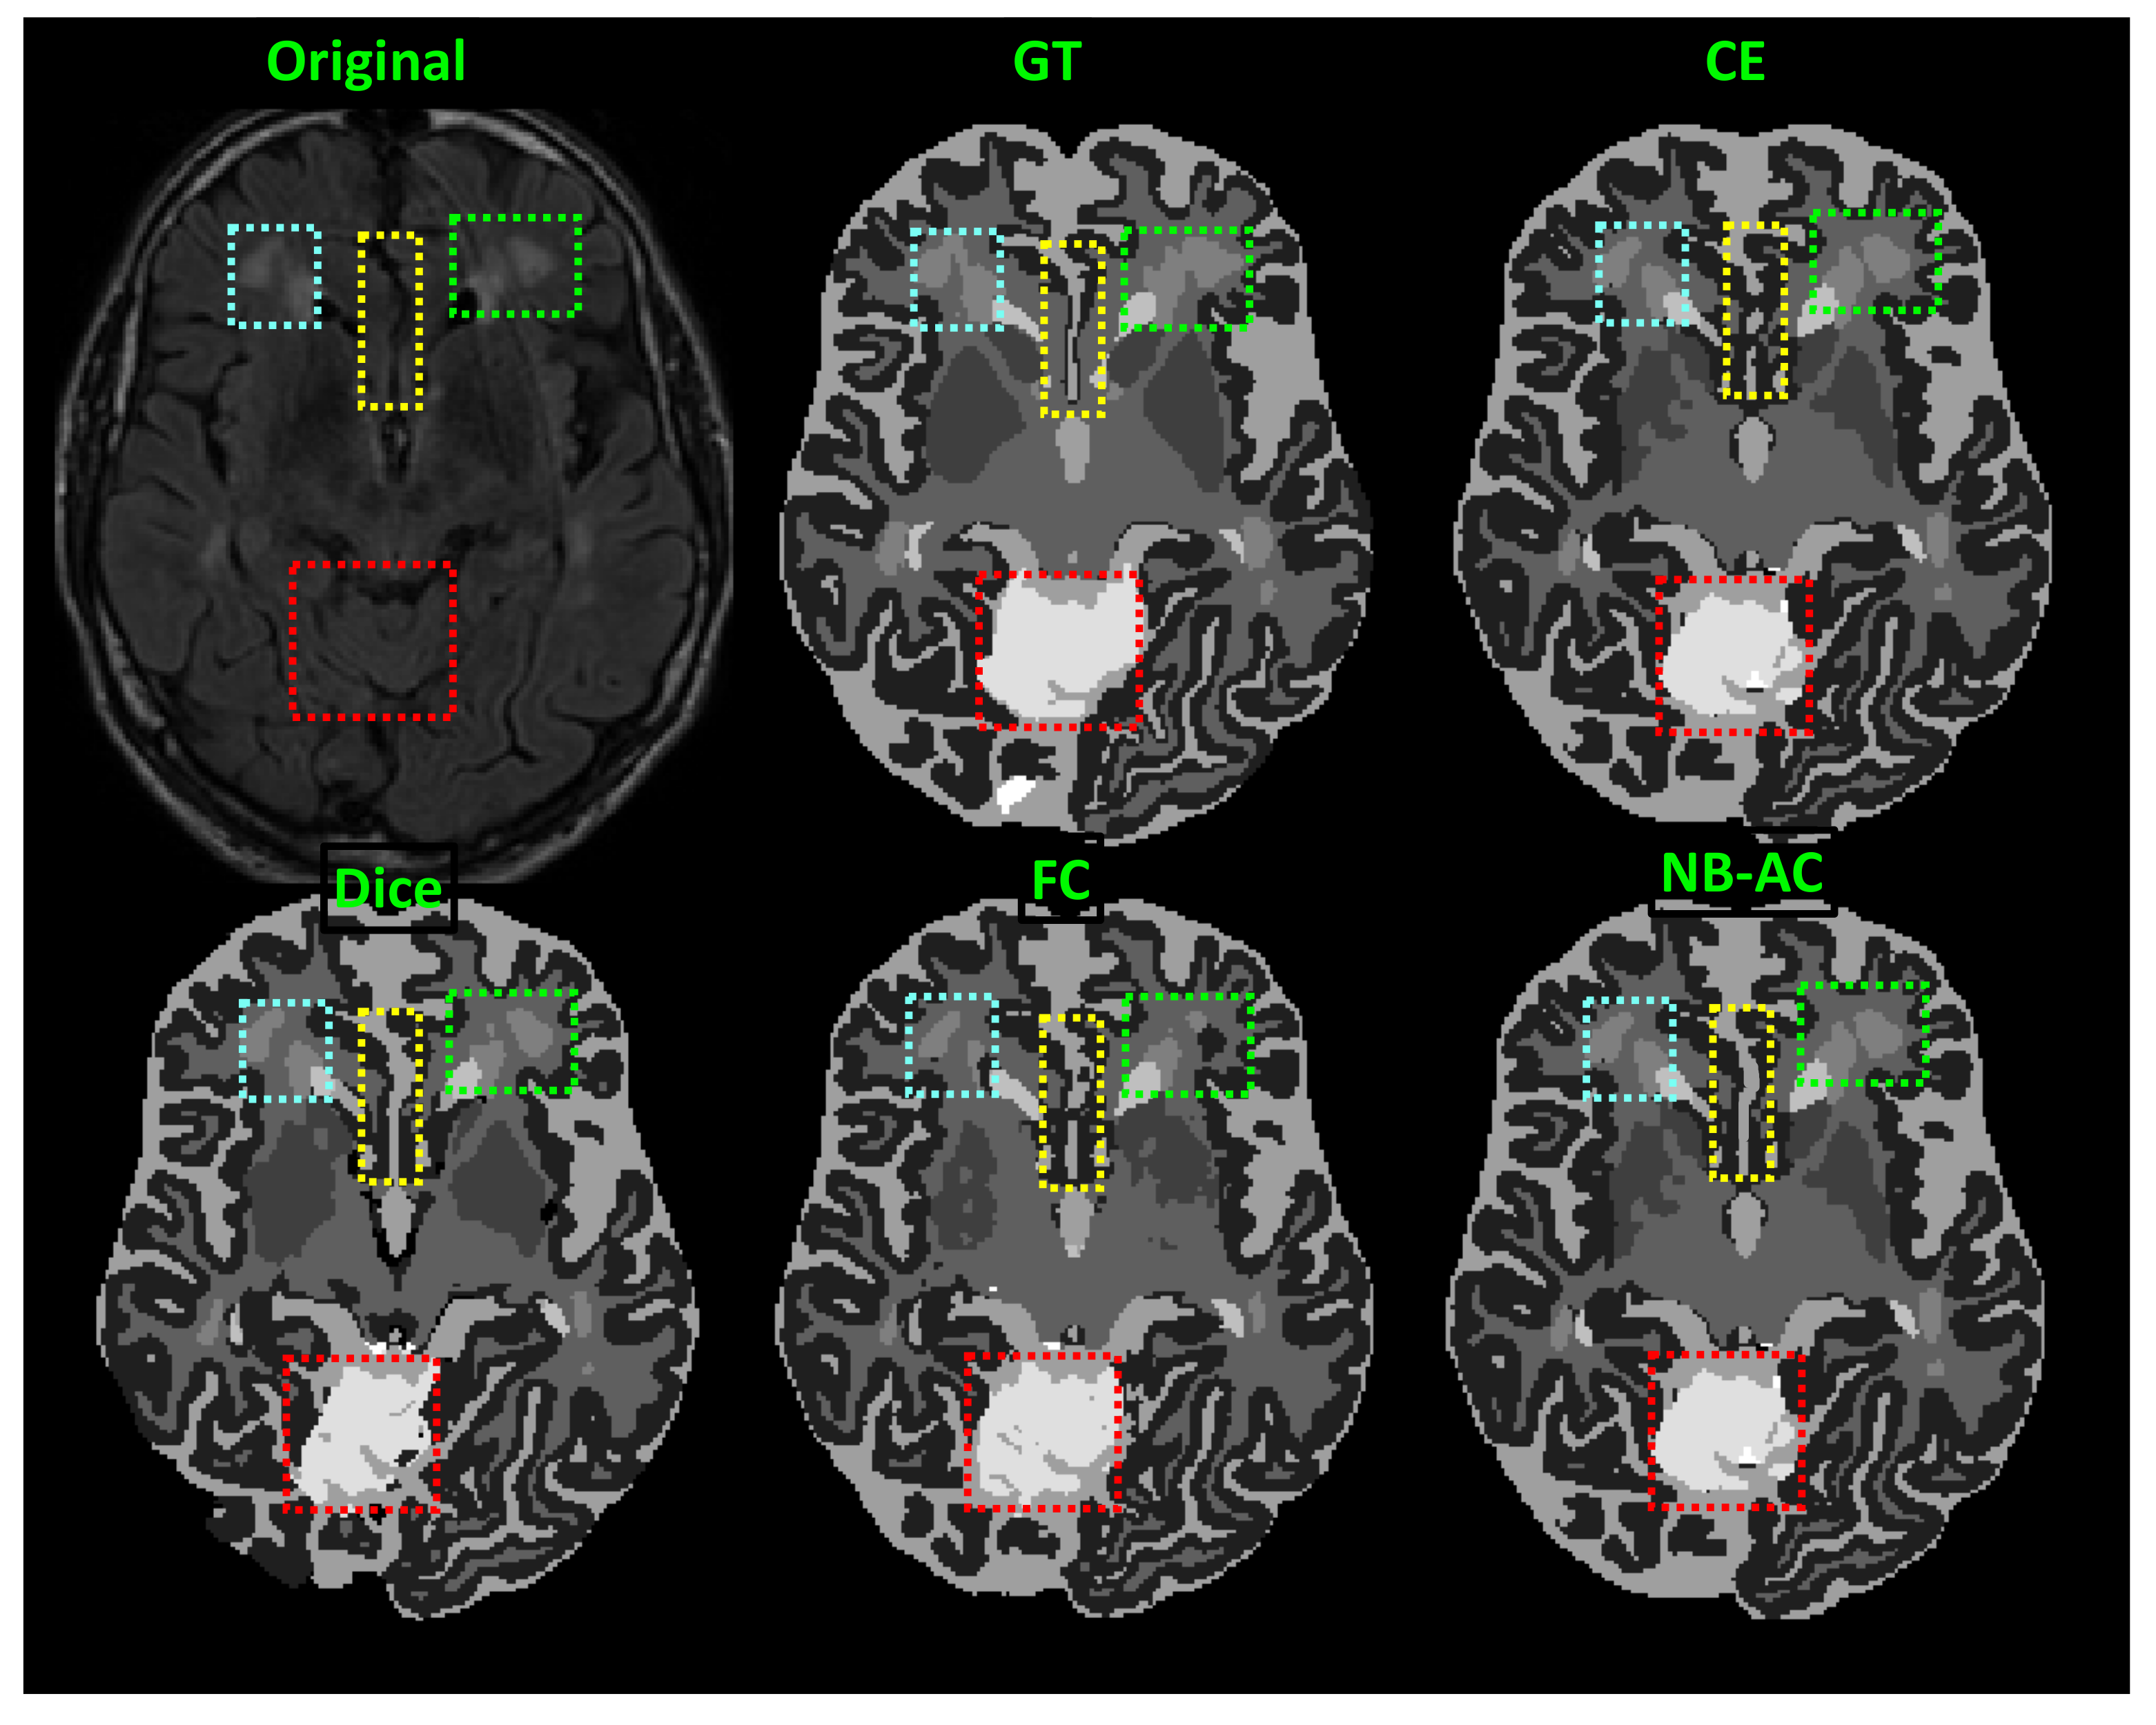

4.4. Results and Comparison